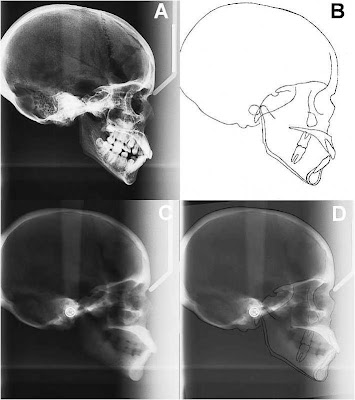

DENTES COM DILACERAÇÃO RADICULAR: REVISÃO DE LITERATURA E APRESENTAÇÃO DE UM CASO CLÍNICO

Pode-se definir dilaceração como uma curvatura anormal entre a coroa e a raiz de um dente completamente desenvolvido.Essa anomalia de desenvolvimento é atribuída a um distúrbio de formação podendo ocorrer tanto na coroa quanto na raiz, onde a parte já calcificada é deslocada em relação à parte não calcificada. A angulação acentuada na raiz ou na coroa de um dente formado pode ocorrer em qualquer ponto ao longo do comprimento radicular (porção apical, média ou cervical), dependendo do estágio da formação radicular, quando ocorrido o trauma. O termo dilaceração dentária pode ainda ser encontrado na literatura como acotovelamento dentário, fratura traumática intrafolicular e luxação traumática intrafolicular.

Como fator etiológico geral atribui-se o trauma dos dentes decíduos, que por sua proximidade com o germe permanente pode provocar seu deslocamento durante a odontogênese, deslocando a parte já calcificada do restante não calcificado, do dente em formação. Entretanto, isso é controverso, pois muitos pacientes não relatam história de trauma na infância e essa deformidade já foi observada em pacientes com agenesia dos dentes decíduos. Além do trauma na dentição decídua, acredita-se também que o tecido de cicatrização, desenvolvido após a perda prematura de um incisivo decíduo, possa ser um obstáculo para a erupção normal do permanente sucessor, o qual altera sua trajetória normal de erupção ocorrendo a dilaceração. Encontra-se citação de pressão exercida por abcessos comprimindo a área radicular de dentes que estão evoluindo na proximidade destes processos inflamatórios. Alguns autores concluíram em seus estudos que a dilaceração se deve simplesmente ao desenvolvimento ectópico do germe do dente permanente.

Um dos primeiros sinais clínicos de dilaceração é observado na erupção de apenas um incisivo central, sem acometimento semelhante com relação a seu homólogo. O forte impacto causado pela ausência clínica do incisivo central superior permanente sobre a estética, nos obriga a refletir sobre a intervenção ortodôntica precoce, ainda na dentadura mista, com o objetivo de compor a harmonia do sorriso.

Dois tipos de dilaceração radicular são descritos: dentes malformados com angulação vestibular da raiz, os quais ficam geralmente impactados e dentes com angulação lateral da raiz que em sua maioria erupcionam espontaneamente1. A terapêutica atribuída a dentes impactados e dilacerados pode ser a exodontia do dente, ou ortocirúrgico, o qual envolve a exposição cirúrgica do dente não erupcionado e o seu tracionamento ortodôntico.

Duas técnicas cirúrgicas usadas para o tracionamento de dentes impactados são citadas na literatura: a técnica do retalho gengival reposicionado apicalmente e a técnica do retalho reposicionado em sua posição original. Dessas duas, a segunda tem oferecido melhores resultados tanto do ponto de vista periodontal quanto estético.

Com relação ao tracionamento ortodôntico, alguns cuidados devem ser tomados, como a utilização de forças suaves, para não comprometer a vitalidade do dente e a perda de osso na região cervical, obtendo ao final do processo, além do sucesso uma estética agradáve. A taxa de sucesso para o tratamento destes dentes impactados e dilacerados depende do grau de dilaceração, da posição do dente e do estágio de formação radicular do mesmo. Uma raiz dilacerada com ângulo obtuso, posição baixa e incompleta formação radicular teria um melhor prognóstico para tracionamento ortodôntico. Os insucessos para este tipo de tratamento se deve, principalmente, a processos de anquilose, reabsorção radicular externa e exposição radicular vestibular ou lingual após tracionamento ortodôntico.

CONCLUSÃO

• No caso clínico relatado, obteve-se um bom resultado clínico e funcional do incisivo central dilacerado após o tracionamento.

• O tratamento combinado ortodôntico-cirúrgico de dentes com dilaceração radicular é uma alternativa viável e deve ser tentado sempre que possível, pois na maioria das vezes envolve a estética.

• A exodontia do elemento dental dilacerado apresenta-se como uma postura radical que resultará num tratamento reabilitador futuro para o paciente. O planejamento sempre possível deve ser o tracionamento do dente para a posição correta dentro do arco dentário.

• A exodontia, apesar de radical, não deve ser descartada nos casos onde a falta de espaço irá requerer a remoção de um elemento dental saudável.